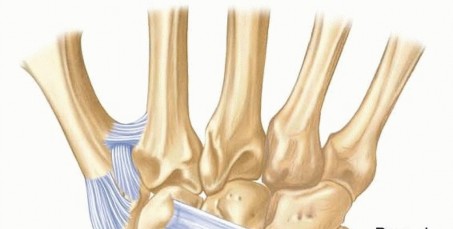

Image

Trapezial fractures are divided into ridge and body fractures, each requiring a distinct approach. Trapezial ridge fractures, analogous to hamate hook fractures, are approached volarly. The incision is made over the FCR tendon, which is carefully retracted. The fracture is exposed, and depending on fragment size, it is either excised (if small and comminuted) or fixed with a mini-fragment screw (if a large, acute basal fragment). Trapezial body fractures, particularly those involving the highly mobile thumb CMC joint, require precise anatomic reduction to prevent early, debilitating arthritis. A dorsal-radial approach is employed, centered over the CMC joint. The radial artery must be identified and protected within the anatomic snuffbox. Fixation is achieved using 1.5mm or 2.0